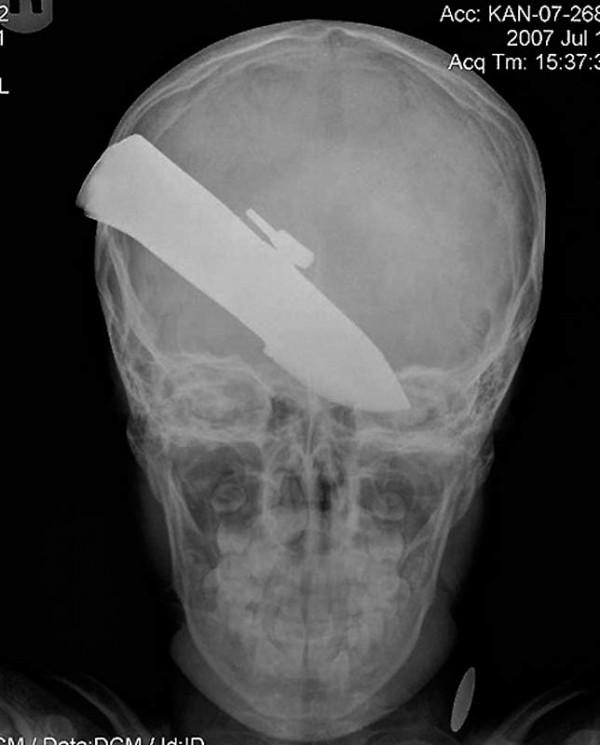

Подросток был ранен ножом в драке, в результате чего 12-дюймовое лезвие вошло в его голову целиком. Парень выжил.

23.